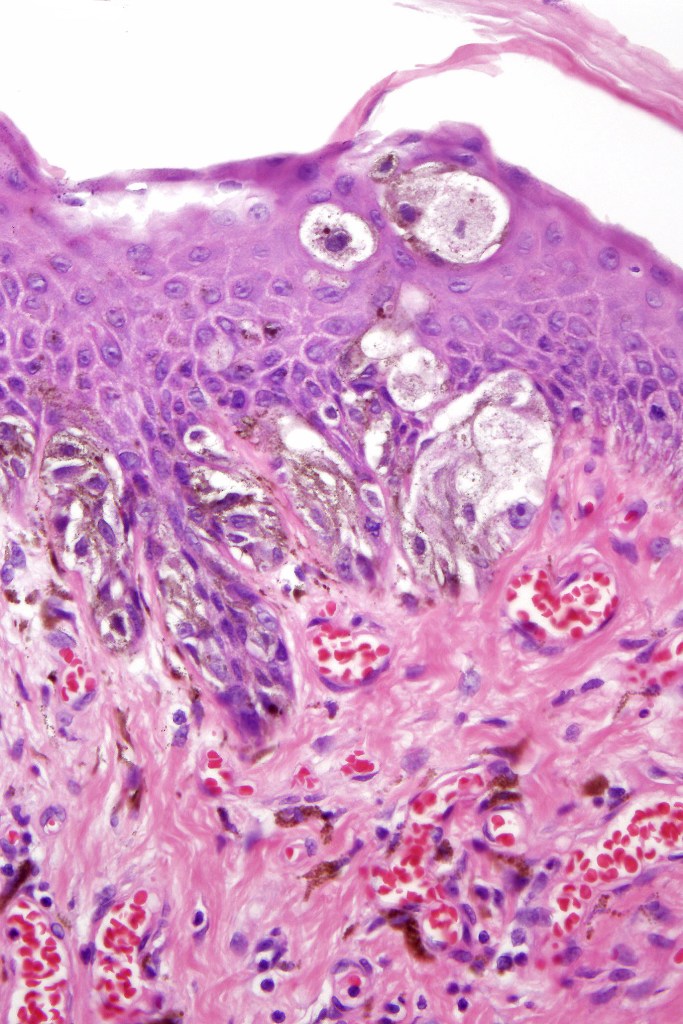

•Heavy pigmentation (sometimes gray/green)

•Variable atypia (can be marked)

•Central pagetoid spread

•Superficial dermal atypia